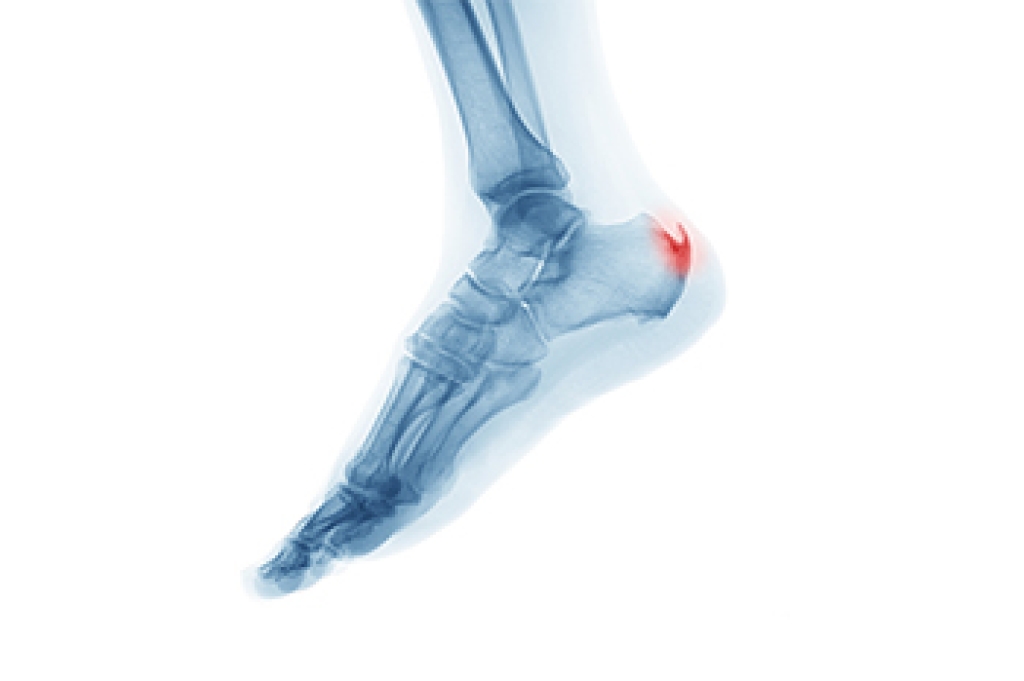

Heel spurs are formed by calcium deposits on the back of the foot where the heel is. This can also be caused by small fragments of bone breaking off one section of the foot, attaching onto the back of the foot. Heel spurs can also be bone growth on the back of the foot and may grow in the direction of the arch of the foot.

Older individuals usually suffer from heel spurs and pain sometimes intensifies with age. One of the main condition's spurs are related to is plantar fasciitis.